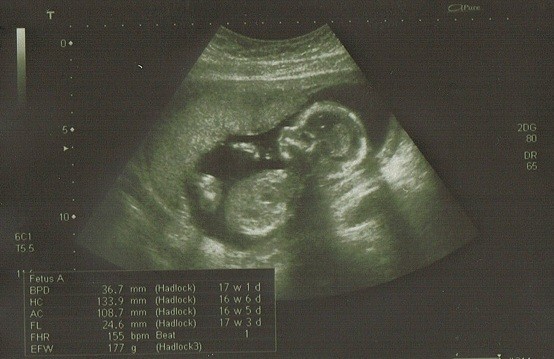

Już po wizycie. Dziękuje wszystkim za kciuki:) Wszystko w porządku, serduszko bije jak dzwon, wymiary prawidłowe, waga też. I najważniejsze:):):)

To DZIEWCZYNKA!!!!:-):-):-)

1.jpgCCF20120404_00000.jpg

Niunia pięknie się ustawiała dzisiaj do zdjęć:):):)